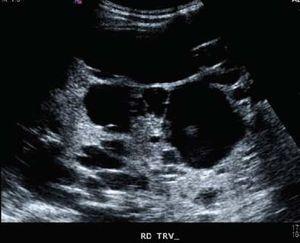

Paciente de 48 años con dolor abdominal en epigastrio, aumento del perímetro abdominal, saciedad temprana, plenitud posprandial y disnea de medianos esfuerzos. El examen físico: T/A: 140/100 IMC: 24.3kg/m², área hepática de 22 cm y hepatodinia. Química sanguínea: Creatinina: 1.06 mg/dL, ALT: 65 UI/L, AST: 28 UI/L, bilirrubina total: 0.67 mg/dL; directa: 0.07 mg/dL. Fosfatasa Alcalina: 60 UI/L.

Ultrasonido y tomografía con evidencia de enfermedad poliquistica del adulto. Se realizó fenestración laparoscopica de los quistes hepáticos, con adecuada evolución.

Figura 2. USG renal: riñón derecho.